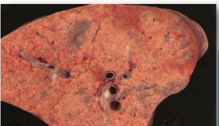

9

Q

A

Enzootic pneumonia caused by Mycoplasma ovipneumoniae

* Slowly progressive, usually non-fatal

* Clinical signs: cough and reduced growth rates

* May be incidental finding at slaughter

* Carcass: small white foci with areas of purple heavy lung

* Lesions are i the cranioventral lung lobes